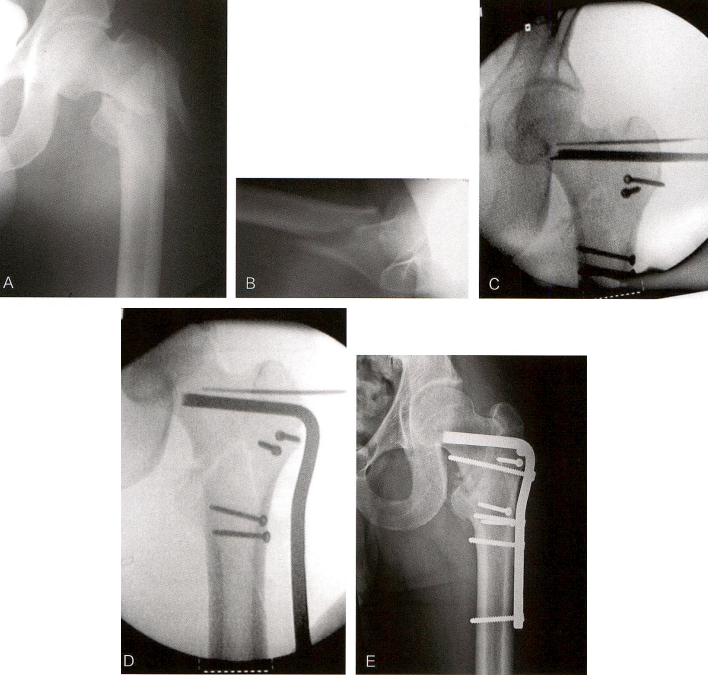

通常选用2~4孔的钢板进行固定(技术图3)。多项临床与尸体研究证实,选用4孔以上的钢板对固定强度无明显提高。内植物要按制造商的相关规范进行安装。在中心套筒的引导下,沿导针置入空心拉力螺钉,确保螺钉打入合适位置。如此前所强调的,要仔细评估所需拉力螺钉的长度,来确保骨折端加压不会使得螺钉过长和尾部突出。

技术图3 置入内固定。A.安装于把手的拉力螺钉和侧方钢板。B.放置侧方钢板。C.内固定在位。D.松开牵引。E.骨折端加压后。

利用透视和手法来确保拉力螺钉拧人时骨折端不移位(旋转)。若拧人拉力螺钉时骨块发生移位,移除该拉力螺钉,置人一枚防旋钉,重新扩孔再打人拉力螺钉。当顺时针方向拧入拉力螺钉时,由于髋部的解剖形态以及拧入螺钉造成的髋关节囊紧张,右髋转子间的骨折尖易向后成角,左侧则易向前成角。在正、侧位透视上确认拉力螺钉拧至股骨头的预想深度后,需确认尾部与外侧皮质的关系,确保长度合适,螺钉的理想位置为尾部深于外侧皮质约5~8mm。而后沿拉力螺钉滑入侧方钢板,将其放置于股骨外侧皮质上,再取出导针和防旋针(若使用)。此时松开牵引,使得骨折端在轴位得到一些加压。经钢板打入骨皮质螺钉,将钢板固定在股骨干上。如果骨折类型符合,透视下在拉力螺钉后方孔内置人加压螺钉,使骨折端沿拉力螺钉长轴进一步加压。有些病例可以去掉这枚加压螺钉。若骨折端对位良好,后续负重时会对骨折区产生加压效果,此时去除该加压螺钉是合理的,但对于瘫痪的患者则必须强制使用并保留该加压螺钉,这类患者的髋关节内不会产生反作用力,所以在术后转运时会发生内固定松动。完成骨折端加压后,再次透视确认力线和内固定的位置。